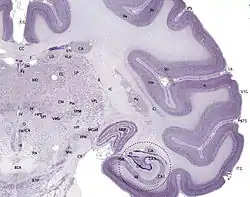

brainmaps.org, CC-BY-SA 3.0

The hippocampus can be seen as a ridge of gray matter tissue, elevating from the floor of each lateral ventricle in the region of the inferior or temporal horn.[12][13] This ridge can also be seen as an inward fold of the archicortex into the medial temporal lobe.[14] The hippocampus can only be seen in dissections as it is concealed by the parahippocampal gyrus.[14][15] The cortex thins from six layers to the three or four layers that make up the hippocampus.[16]

The term hippocampal formation is used to refer to the hippocampus proper and its related parts. However, there is no consensus as to what parts are included. Sometimes the hippocampus is said to include the dentate gyrus and the subiculum. Some references include the dentate gyrus and the subiculum in the hippocampal formation,[1] and others also include the presubiculum, parasubiculum, and entorhinal cortex.[2] The neural layout and pathways within the hippocampal formation are very similar in all mammals.[3]

The hippocampus, including the dentate gyrus, has the shape of a curved tube, which has been compared to a seahorse, and a ram's horn (Cornu Ammonis). Its abbreviation CA is used in naming the hippocampal subfields: CA1, CA2, CA3, and CA4.[15] It can be distinguished as an area where the cortex narrows into a single layer of densely packed pyramidal neurons, which curl into a tight U shape. One edge of the "U," – CA4, is embedded into the backward-facing, flexed dentate gyrus. The hippocampus is described as having an anterior and posterior part (in primates) or a ventral and dorsal part in other animals. Both parts are of similar composition but belong to different neural circuits.[17] In the rat, the two hippocampi resemble a pair of bananas, joined at the stems by the commissure of fornix (also called the hippocampal commissure). In primates, the part of the hippocampus at the bottom, near the base of the temporal lobe, is much broader than the part at the top. This means that in cross-section the hippocampus can show a number of different shapes, depending on the angle and location of the cut.

In cross-section of the hipppocampus, including the dentate gyrus, several layers will be shown. The dentate gyrus has three layers of cells (or four if the hilus is included). The layers are from the outer in - the molecular layer, the inner molecular layer, the granular layer, and the hilus. The CA3 in the hippocampus proper has the following cell layers known as strata: lacunosum-moleculare, radiatum, lucidum, pyramidal, and oriens. CA2 and CA1 also have four each of these layers and not the lucidum stratum.